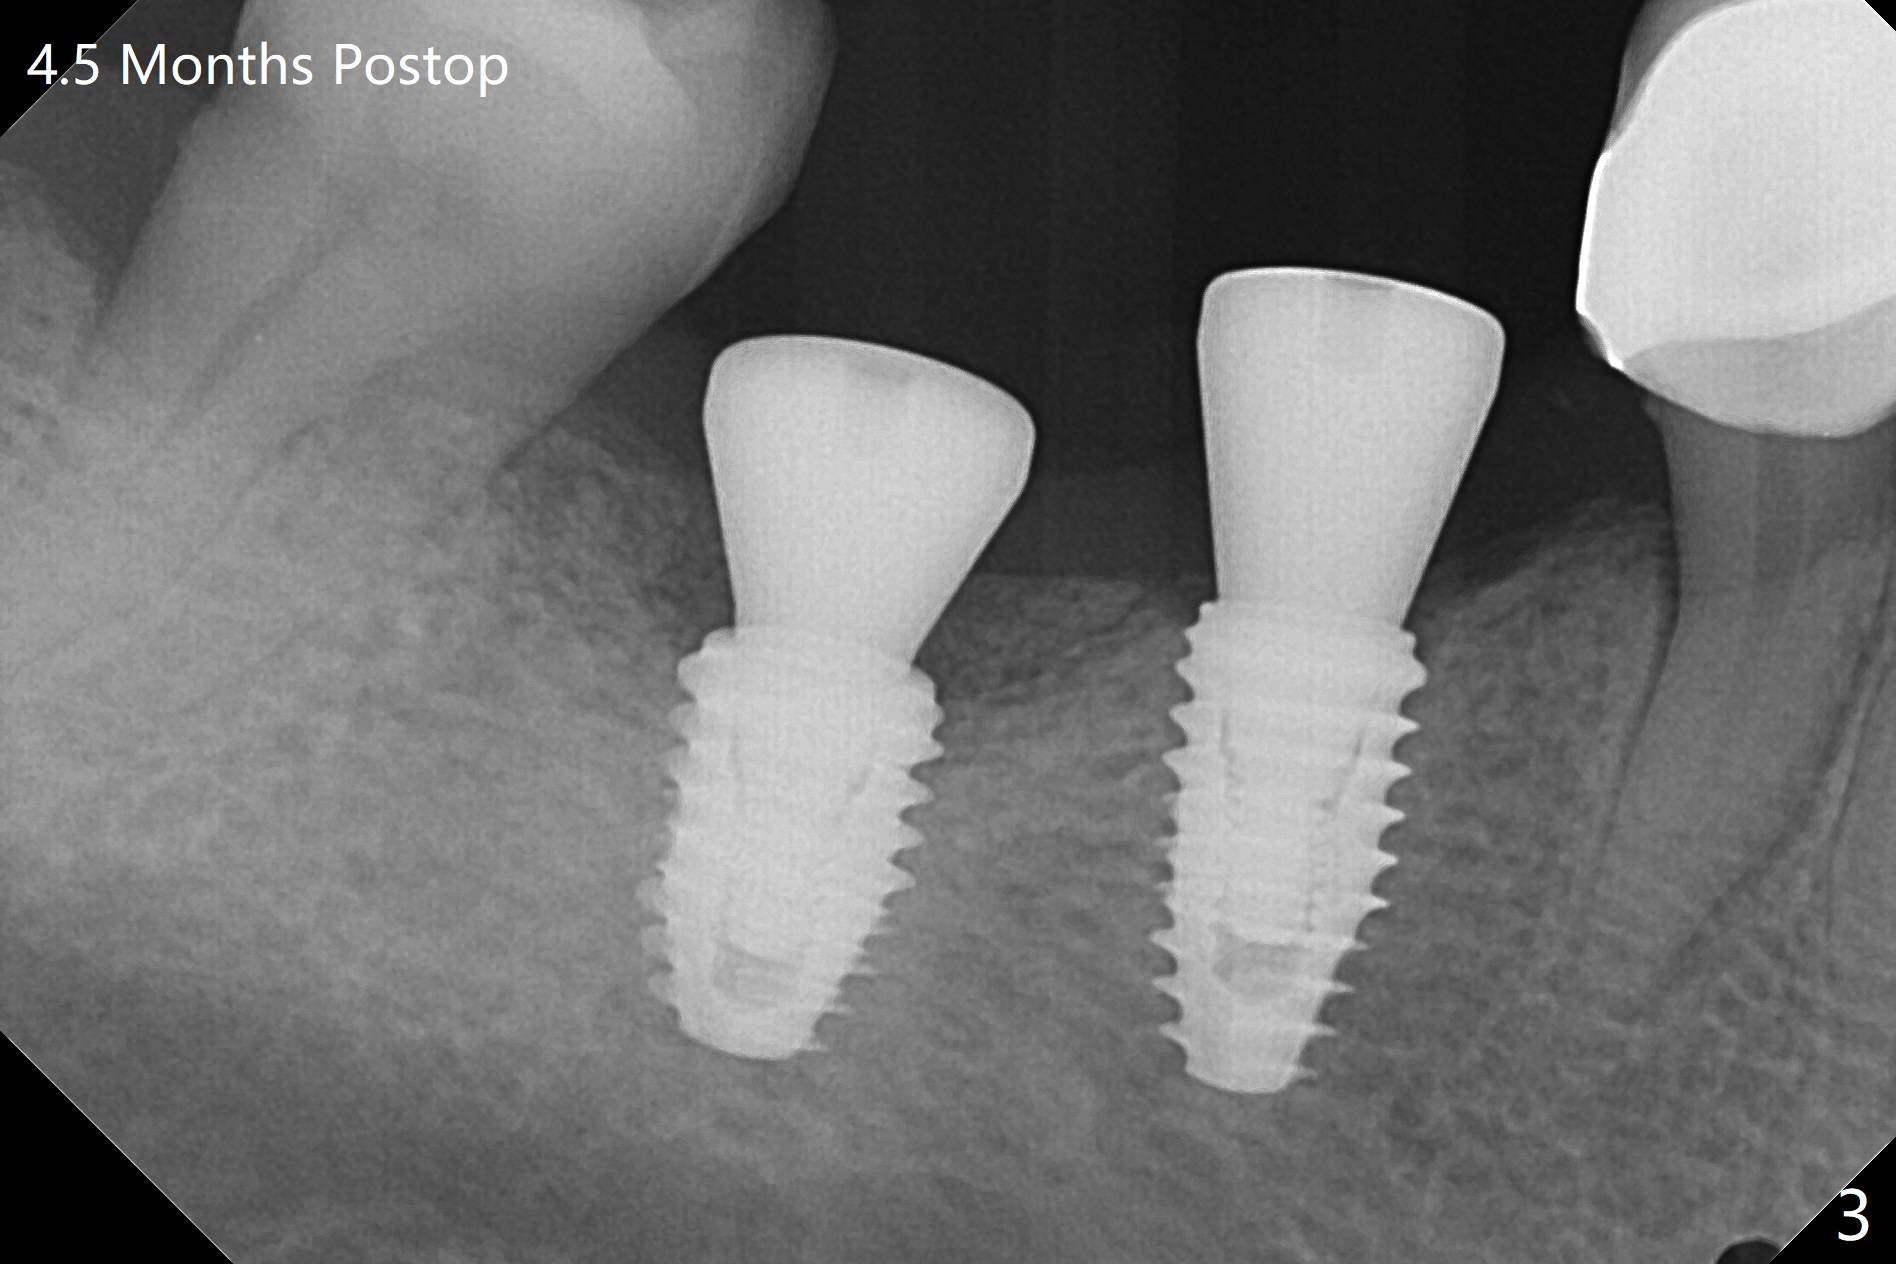

With one carpule of Xylocaine 34 mg with Epinephrine 17 mcg (infiltration) and slow osteotomy with guide, two short implants are placed at #29 and 30 painless with >45 Ncm (Fig.1). Healing abutments are placed without bony interference (Fig.2). It appears that the tooth #31 shifts mesially (Fig.2 arrow), which should be slowed down and/or corrected with early provisional. There is no bone loss 4.5 months postop (Fig.3). With placement of 4.5x4.5(3) and 5.2x4.5(4) mm abutments at #29 and 30, respectively, no limited orthodontic treatment seems to be needed. The screw at #29 becomes loose 4 months post cementation and a few days after #19 implant is loose (bruxism). In fact this is not completely true, since the abutment at #29 is incompletely seated (Fig.4). The abutment at #30 is also incompletely seated because of the vertical gap (<), probably due to mesial and distal crestal interference (*).